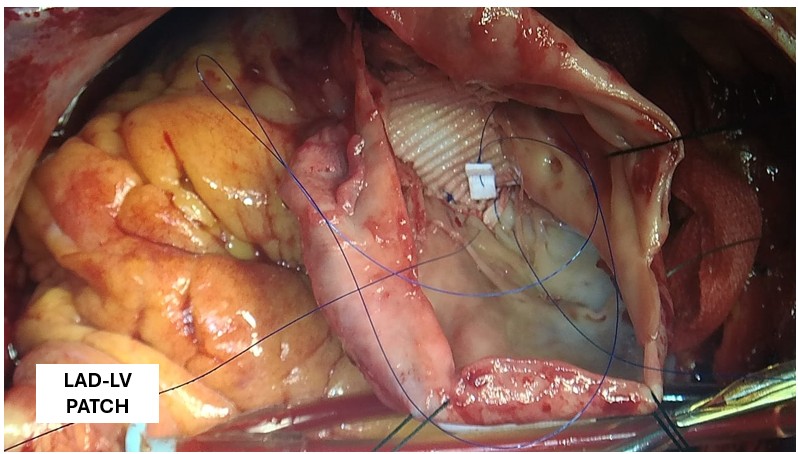

A covered stent was deployed in the distal LAD in an attempt to seal the coronary perforation; however, angiography showed that the Type III perforation persisted despite the intervention. Additional balloon inflation within the stent was performed, but the leakage could not be completely sealed. The patient remained hemodynamically stable without signs of cardiac tamponade or pericardial effusion. The following day, repeat coronary angiography was conducted to reassess the condition, which confirmed persistent contrast extravasation from the LAD into the left ventricular cavity, indicating the formation of a coronary–ventricular fistula. Given the hemodynamic significance and the risk of progressive left ventricular dysfunction due to continuous shunting, a multidisciplinary decision was made to proceed with surgical correction. The patient subsequently underwent successful LAD–LV fistula patch repair combined with. Surgical repair remains the definitive management for such cases, and early recognition with timely intervention is crucial to restore cardiac function and prevent irreversible myocardial damage.

The patient underwent successful surgical patch closure of the LAD–LV fistula along with ventricular reconstruction to restore myocardial integrity. The postoperative recovery was smooth and uneventful, with stable hemodynamics throughout hospitalization. Follow-up echocardiography demonstrated significant improvement in LVEF to 53%, and she remained asymptomatic during subsequent outpatient follow-up